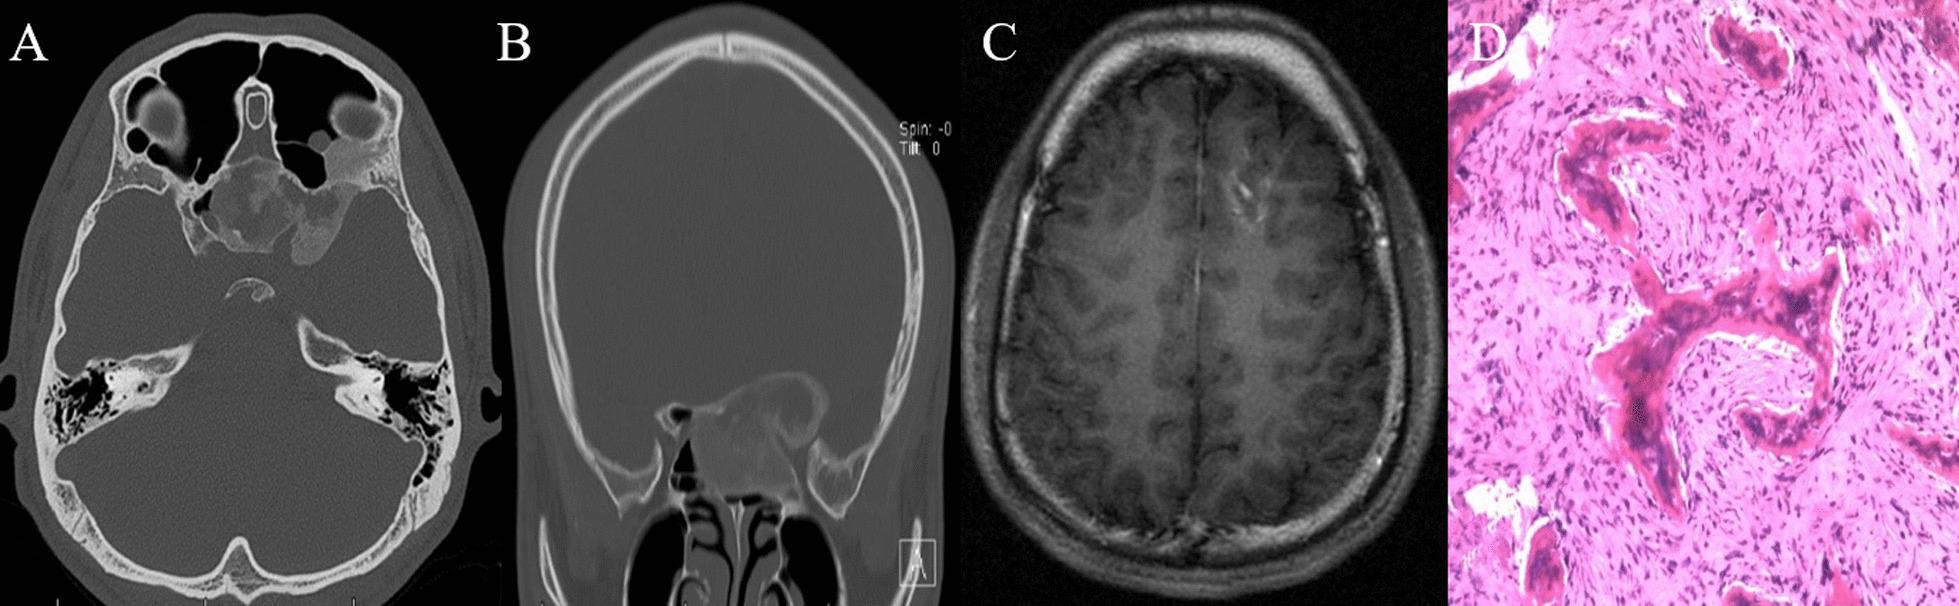

22 out of 1175 patients (1.9%) were diagnosed with craniofacial fibrous dysplasia and cerebrovascular diseases including 9 intracranial aneurysms, 4 venous malformations, 2 arteriovenous malformations, 1 moyamoya disease, 2 intracranial venous stenosis and 4 cerebral ischemia with a mean age of 38.18 years old. Only 2 patients were managed surgically for craniofacial fibrous dysplasia and 6 patients were treated with neurosurgery for cerebrovascular diseases. 8 patients were closely followed and only 1 patient's symptoms worsened.

1175例患者中有22例(1.9%)被诊断为颅面骨纤维发育不良合并脑血管疾病,包括9例颅内动脉瘤、4例静脉畸形、2例动静脉畸形、1例烟雾病、2例颅内静脉狭窄和4例脑缺血,平均年龄为38.18岁。仅2例患者因颅面骨纤维发育不良接受了手术治疗,6例患者因脑血管疾病接受了神经外科治疗。8例患者进行了密切随访,只有1例患者症状加重。